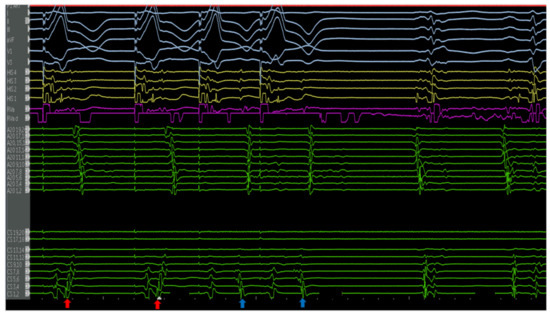

4.2.1. Cases

4.2.3. Case 2